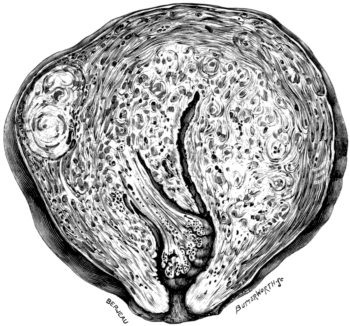

| 23. | A Gravid Uterus in Sagittal Section | 79 |

| 22. | A Uterus distorted by Fibroids | 76 |